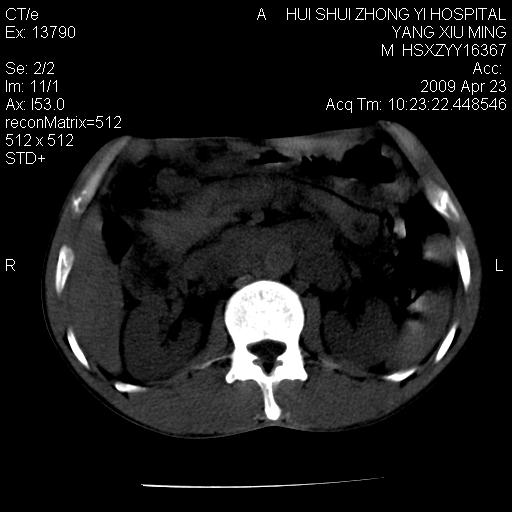

上腹部疼痛一月,呕吐10天,发现左侧颈部包快10天 胸部cr片未见明显异常。

腹膜后淋巴结增大,转移、淋巴瘤?胰腺增大,胰腺炎?占位?颈部考虑增大淋巴结。建议腹部增强扫描。

缺少强化资料,暂考虑胰腺癌广泛转移.

连最基本的ct值都没有测        腹部的窗宽窗位太大了     影响诊断

黑!广泛淋巴结肿大不符合胰腺癌转移。胰腺周围淋巴结肿大致使胰腺看起来大。考虑淋巴瘤可能大。